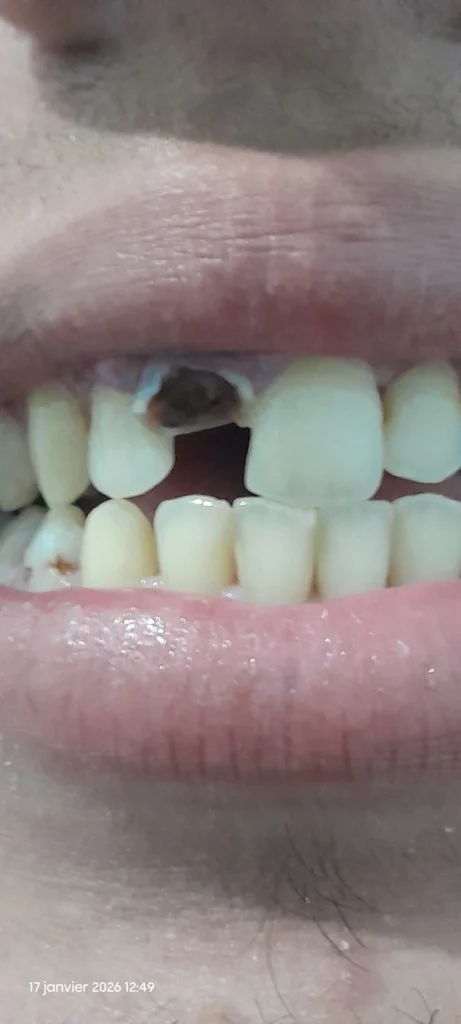

سنة امامية مكسورة

تكسرة لي سنة كبيرة امامية نصفها يتحرك كثيرا والنصف الاخر مازال مغروسا مكانه النصف المكسور باقي في مكانه

Dentiste ? Connectez-vous et contribuez à la communauté dentaire au Maroc

Se connecterSalam Mohamed , KHASSEK TMCHI 3ND TBIB A9RAB WA9T MOMKIN HIT DIK SENNA T9DER TMOUT IDAN KHASSNA N9ATLOU L3AR9 O 3AL 2AGHLAB TGHALAF